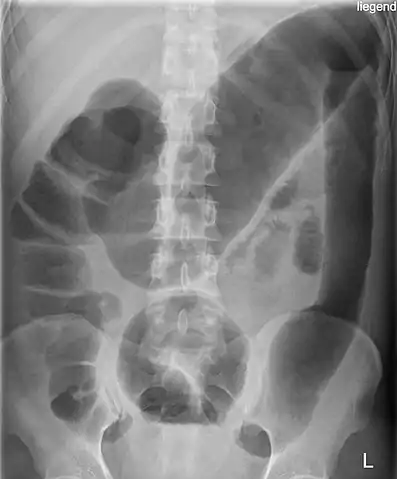

Abdominal X-ray with the features of Air-fluid level can be shown or CT Scan with Contrast can be done if the patient is stable.

Toxic megacolon (and an appendiceal-sigmoid fistula).

Toxic megacolon in a patient with ulcerative colitis: The patient subsequently underwent a colectomy.